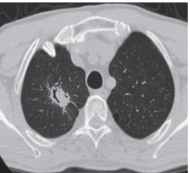

Симптом воздушного полумесяца

Air crescent sign (син.: симптом серповидной полоски воздуха)Семиотика. Рентген, КТ

Щелевидная полость в виде полумесяца или серпа, представляет собой патологическое скопление воздуха, отделяющее содержимое полости тканевой плотности от стенок самой полости.

Симптом серповидной полоски воздуха является признаком мицетомы (обычно аспергиллеза), возникшей в какой-либо ранее существовавшей полости. Примером могут служить эмфизематозные буллы (см.), остаточные полости после абсцесса, туберкулезные каверны и пр. При этом часто наблюдается смещение мицетомы внутри полости при изменении положения тела. Также этот симптом наблюдается в полостях различного генеза при их частичном опорожнении от содержимого, в частности при ангиоинвазивном аспергиллезе, туберкулезной пневмонии и туберкулеме, микроскопическом полиангиите, внутриполостном кровоизлиянии и распадающейся опухоли.